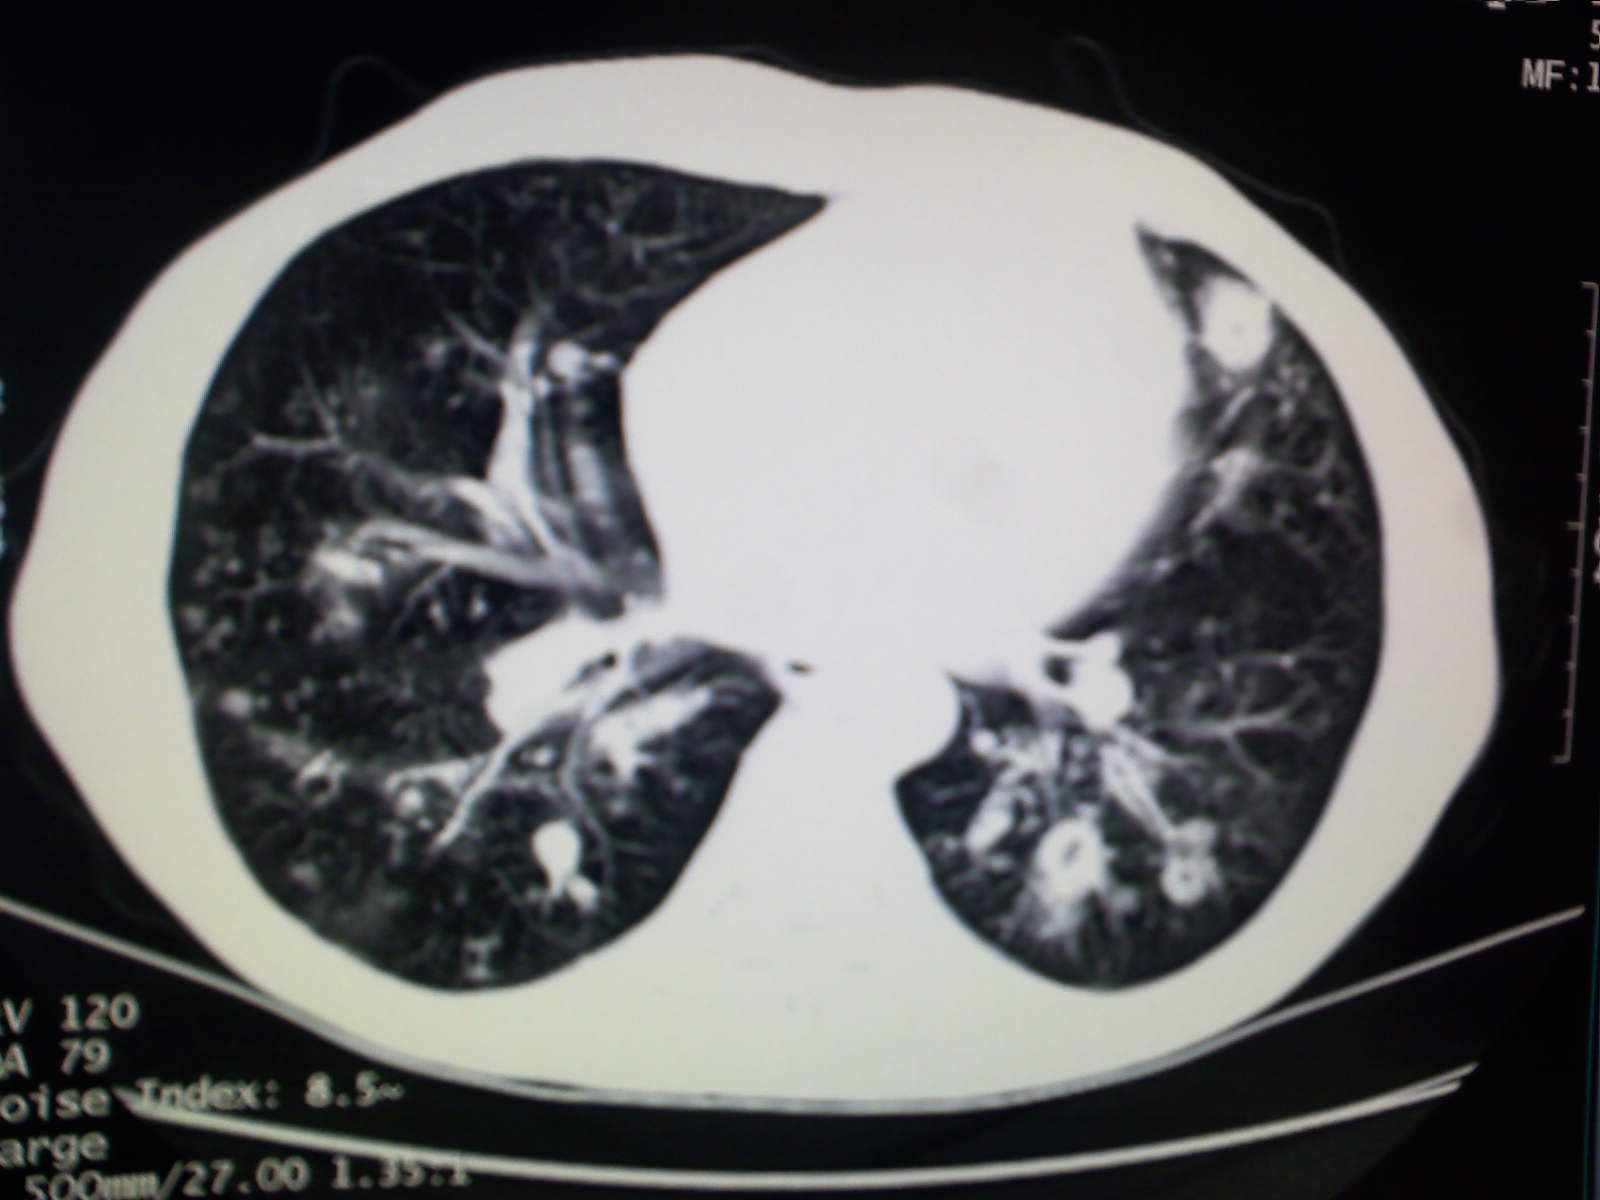

以下是引用卜一在2009-4-11 15:50:00的发言:[br]双肺继发性肺结核伴空洞形成,不排除合并霉菌感染!(病灶呈多形态 多特征 散在分布)。另:合并支气管扩张征伴感染!

以下是引用主力军在2009-4-11 15:55:00的发言:[br]两肺继发性肺结核可能性大。

以下是引用康鹏在2009-4-11 16:30:00的发言:[br]双肺继发性肺结核伴空洞形成合并感染[br]支气管扩张合并感染